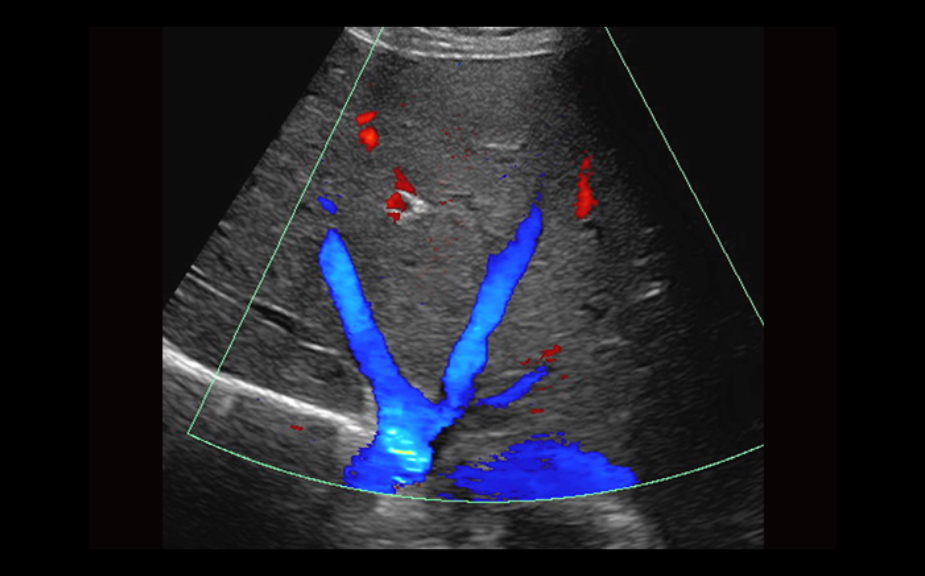

Equipado con software patentado con base en tecnolog├Ła ZONE?Sonography? (ZST),?el Z.One PRO proporciona toma de im├Īgenes Doppler y Modo-B detalladas ├│ptimamente para pacientes, sin importar la complexi├│n del cuerpo, ayudando a asegurar un diagn├│stico confiable.

- Insuperable calidad de imagen en todas las aplicaciones

El Z.One PRO est├Ī dise?ado bas├Īndose en ZONE Sonography Technology, una arquitectura de formaci├│n de im├Īgenes innovadora y registrada que adquiere y procesa informaci├│n ac├║stica hasta 10 veces m├Īs r├Īpido que los m├®todos de formaci├│n de haces convencionales.